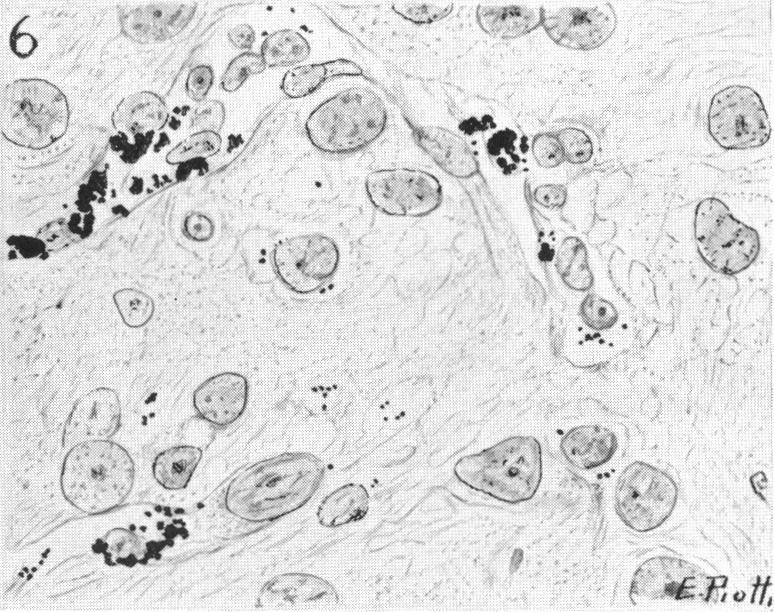

Vital Staining of the Nervous System: I. Factors in the Vital Staining of Neurones.

J Anat. 1935 Jan;69(Pt 2):177-180.1.